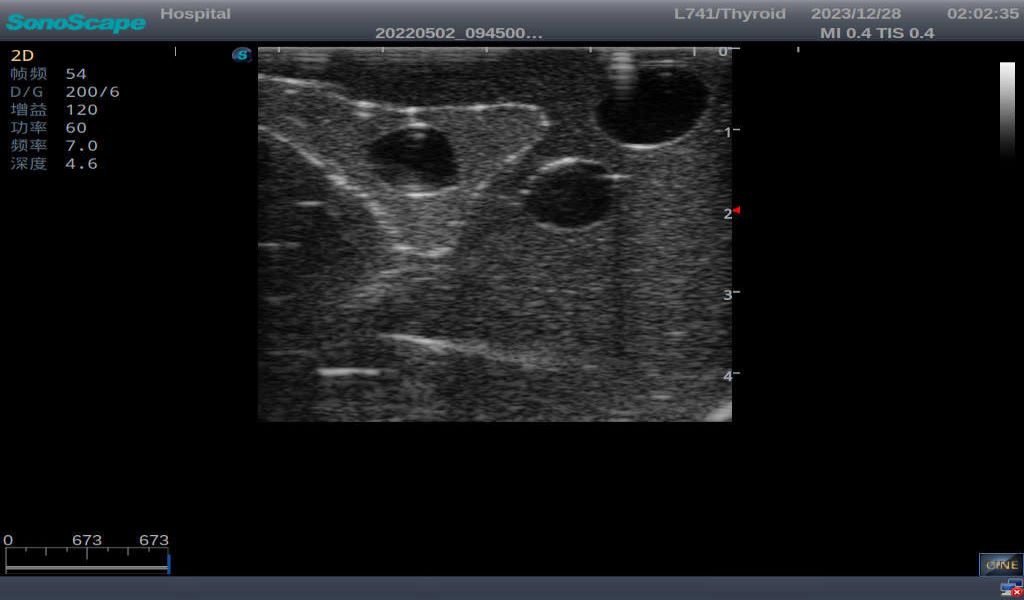

3) It comes with four (4) thyroid modules and can show five (5) ultrasonic images: normal thyroid, thyroid adenoma, thyroid cancer, nodular goiter, thyroid cyst

Nodular goiter with irregular border and varying sizes of low echo, isoechoic, or high echo nodules